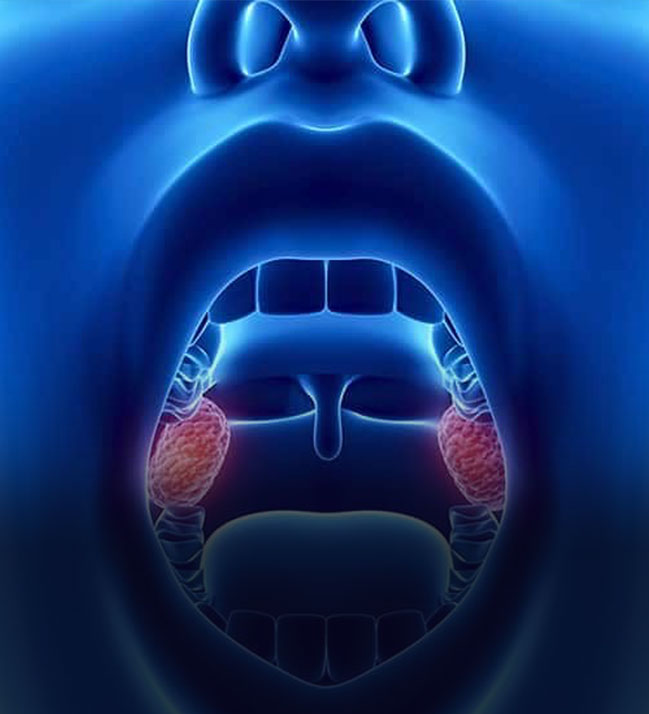

Tonsillektomi

Bademcik Ameliyatı